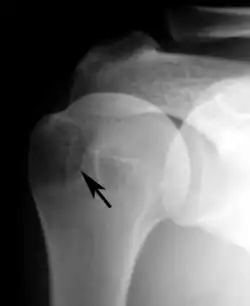

Plain x-rays of the shoulder can be used to detect some joint pathology and variations in the bones, including acromioclavicular arthritis, variations in the acromion, and calcification. However, x-rays do not allow visualization of soft tissue and thus hold a low diagnostic value.[2] Ultrasonography, arthrography and MRI can be used to detect rotator cuff muscle pathology. MRI is the best imaging test prior to arthroscopic surgery.[2] Due to lack of understanding of the pathoaetiology, and lack of diagnostic accuracy in the assessment process by many physicians,[21] several opinions are recommended before intervention.

Plain x-rays of the shoulder may show a “proximal humeral pseudocyst”. This localized area of bone atrophy is the result of increased blood circulation which demineralizes the bone at the attachment of the rotator cuff tendon. It is evidence of chronic inflammation of the rotator cuff. Chronic shoulder inflammation is frequently asymptomatic, and this cystic appearance may be the only evidence of an inflammation.[22][23]